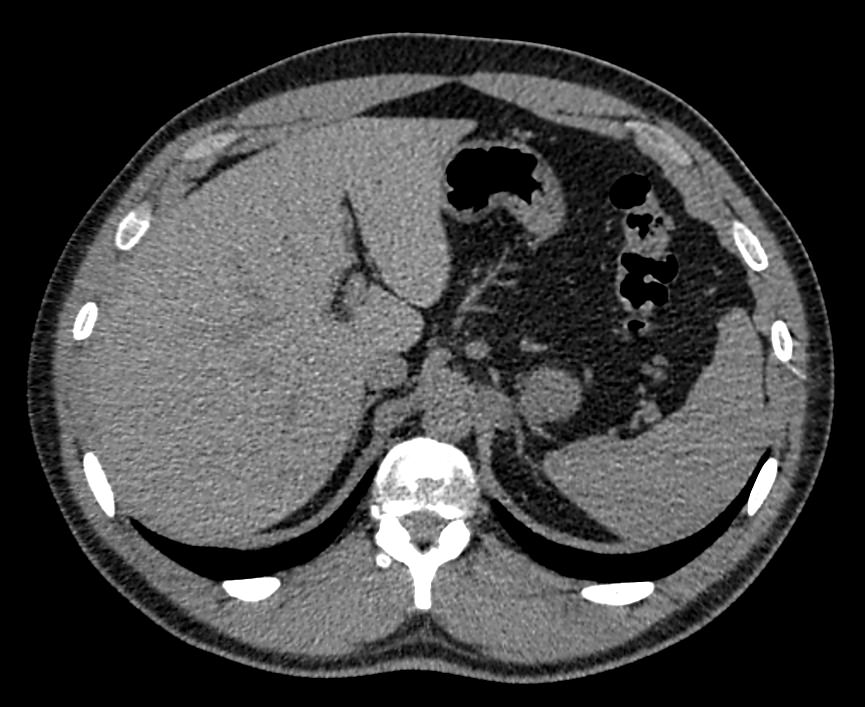

Печеночная ткань имеет обильное кровоснабжение, поэтому часто ультразвуковая диагностика заболеваний печени затруднена. Одним из наиболее информативных методов диагностики является мультиспиральная КТ печени, которая может проводиться в стандартном режиме и с внутривенным болюсным контрастированием. Введение йодсодержащего контрастного вещества значительно повышает диагностическую ценность компьютерной томографии и позволяет, в частности, выявить злокачественное образование на ранней стадии, отличить доброкачественный процесс от злокачественного, визуализировать изменения внутрипеченочных желчных протоков и многие другие патологические процессы.

Обследование печени посредством компьютерной томографии позволяет выявить следующие патологии:

- кисты;

- абсцессы;

- первичные опухоли и метастазы;

- паразитарные заболевания (эхинококкоз, альвеококкоз)